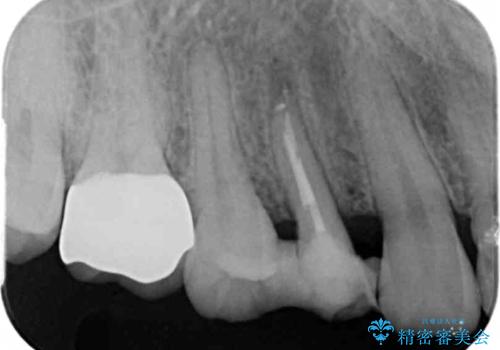

レントゲン画像上で歯茎の深いところまで虫歯になっており、保険治療では抜歯適応になってしまいます。

今回は虫歯の深いところが歯茎のラインにくるまで部分矯正で引っ張り出し、適合の良いかぶせ物を装着しました。

虫歯を取り切った後は、歯を引きあげたことで一緒に上がってきてしまった骨をならしていきます。

その後ラバーダムをして根っこの治療をし、被せ物を被せて治療終了となりました。